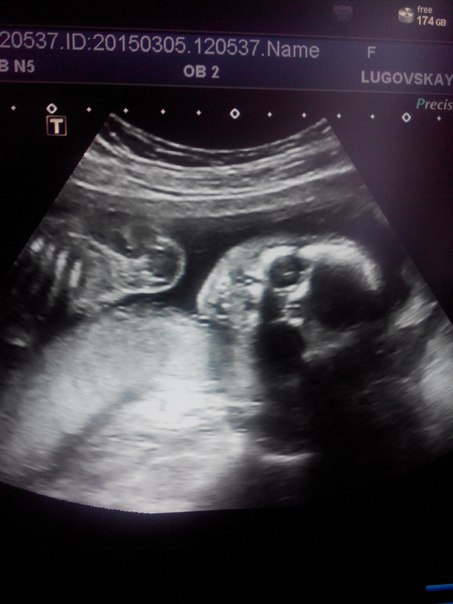

Вот и прошло наше второе узи. И наш маленький пузожитель сделал маме и бабушке самый великолепный подарок. Мы показались со всех сторон и оказалось, что у нас будет прекрасный СЫН.) И звать нас будут Никиткой.) Муж сиял как никогда. Мы были у великолепного врача. Все показатели у нас в норме. Но самое милое было то как он смешно моргал и бултыхал ножками. Теперь будем ждать третьего узи и новой встречи с сыночком.